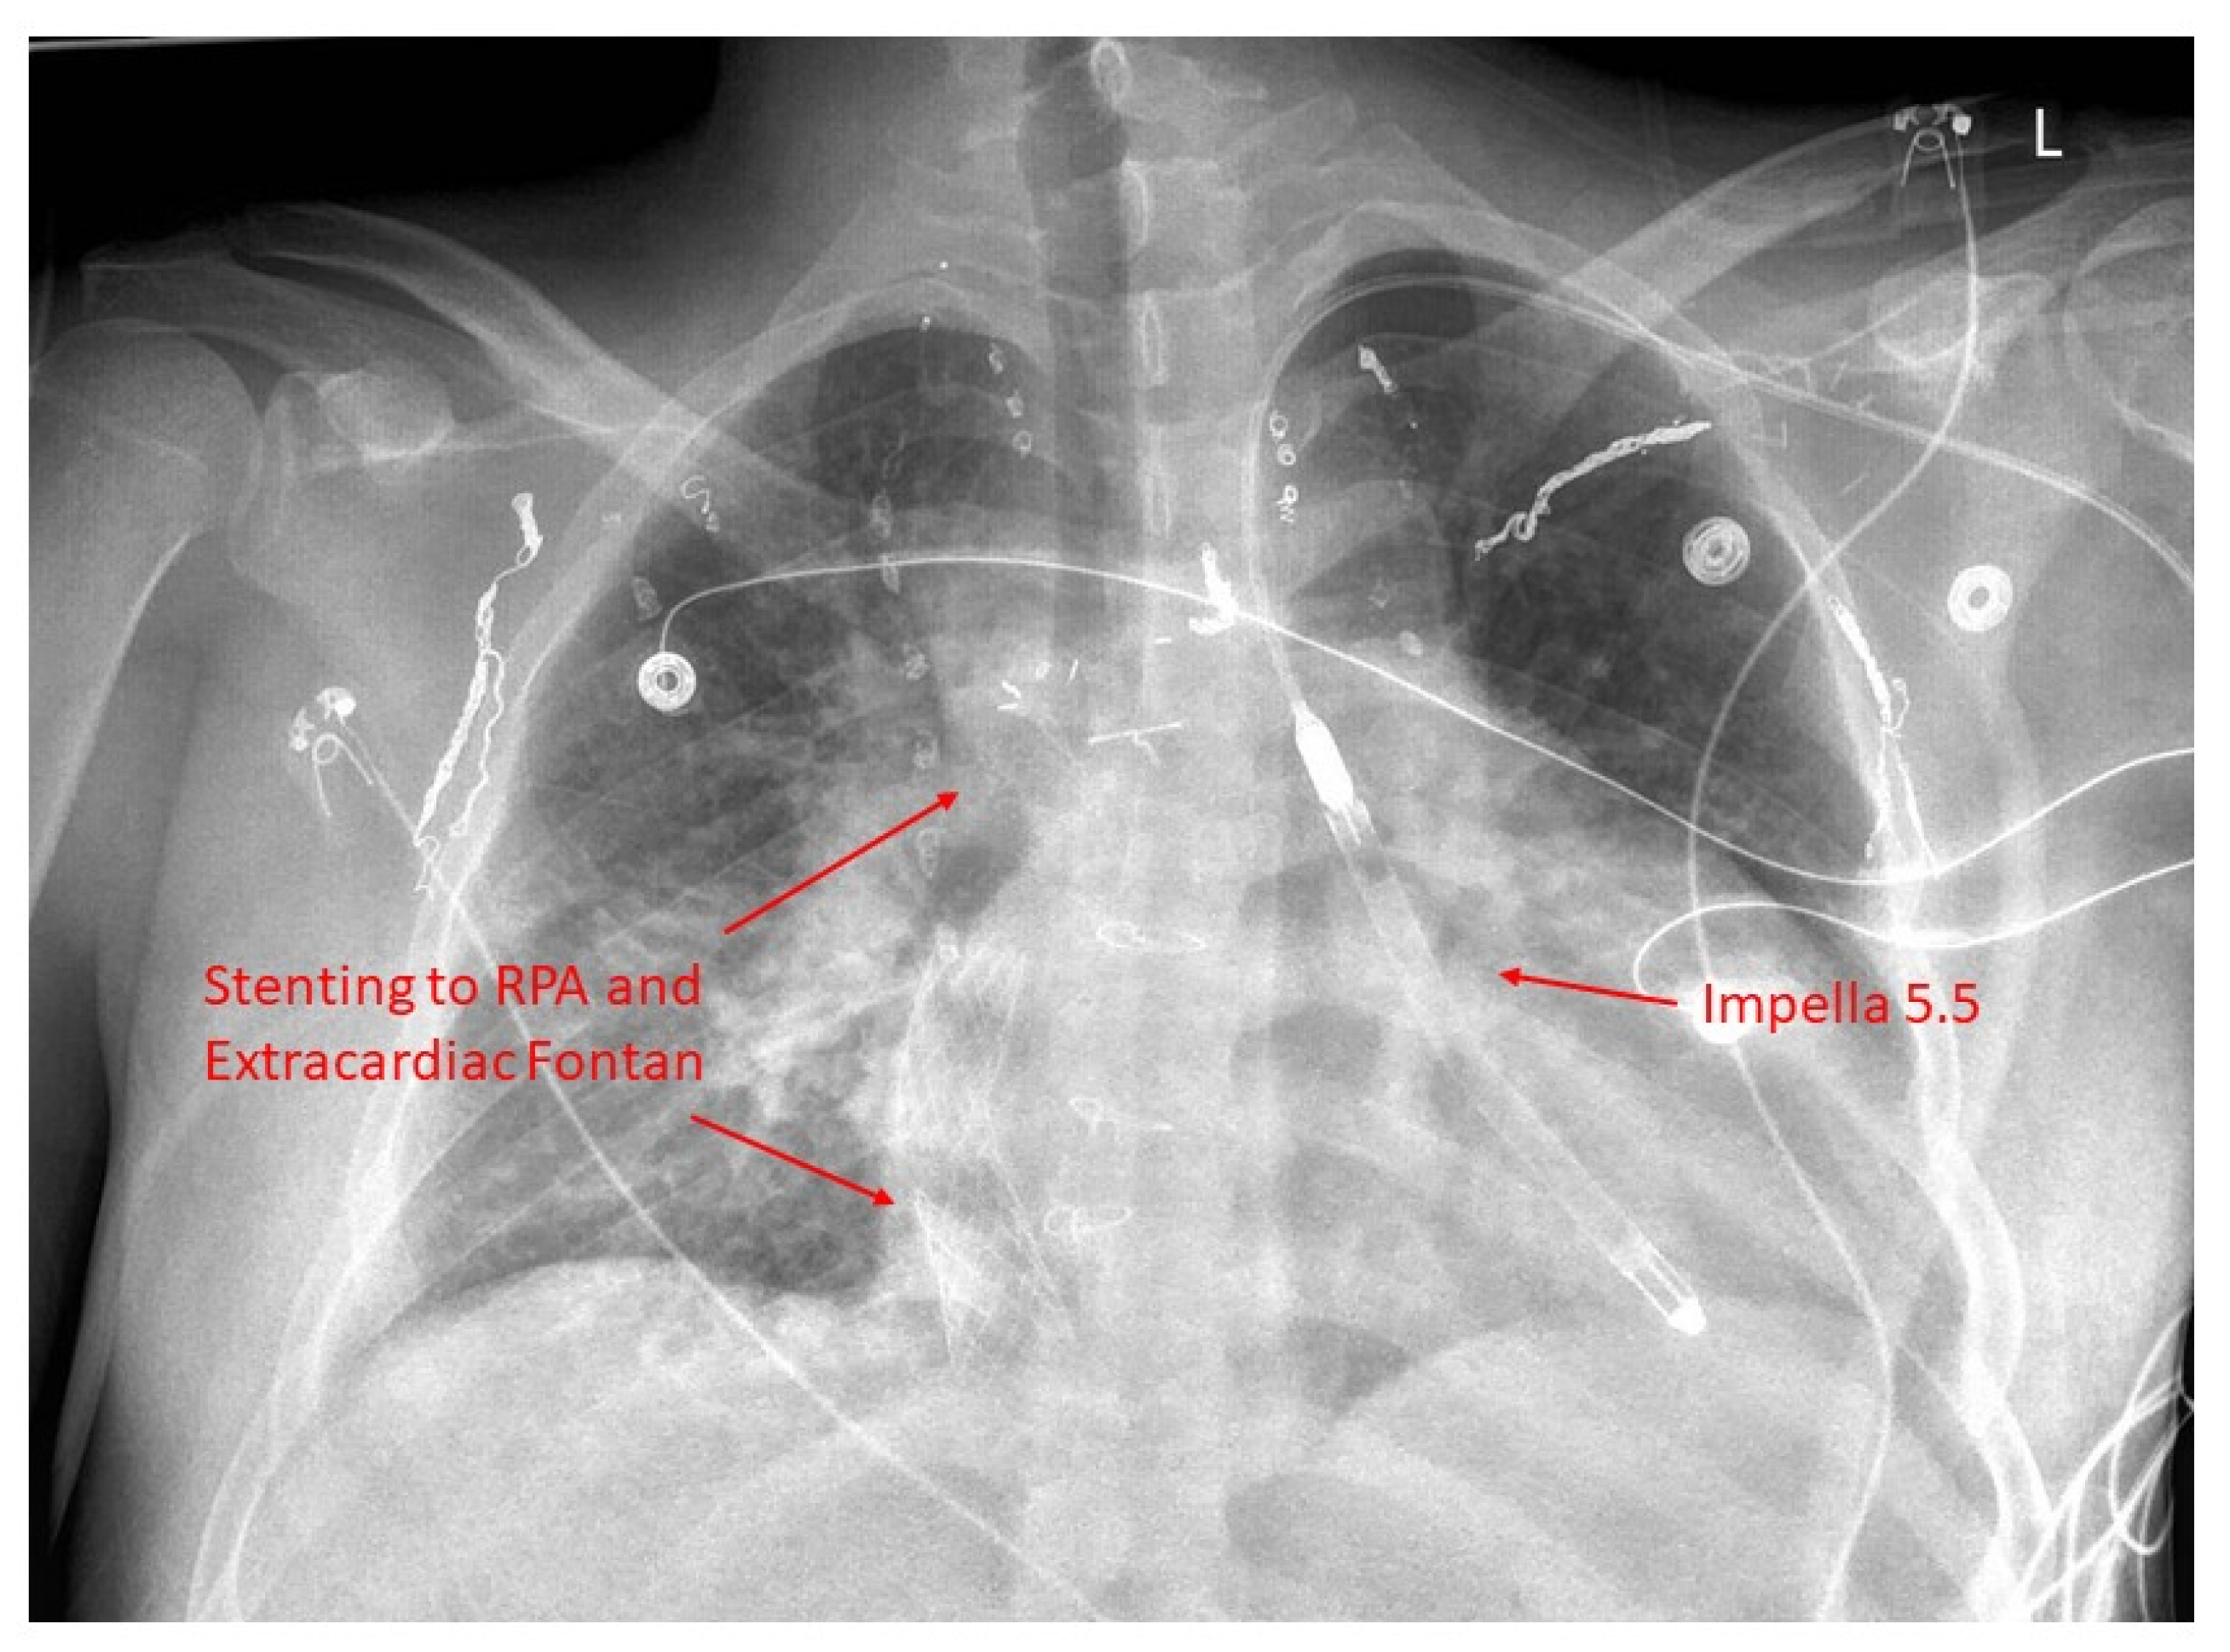

19. Mechanical Circulatory Support

20. Transplantation

22. Fontan Pathway Obstruction